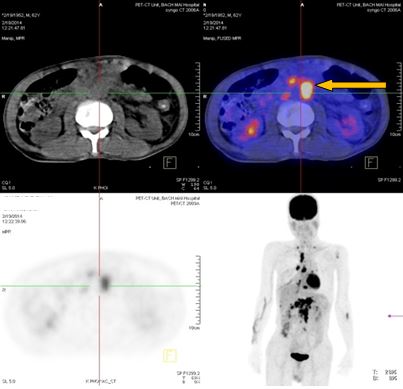

-          Bệnh nhân đã được tiến hành chụp PET/ CT đánh giá, kết quả:

+ Vùng phế quản gốc phải có khối KT 2,4x1,7cm, tăng hấp thu F-18 FDG, max SUV=8,50. Hạch trung thất kích thước lớn nhất 3,1x3,5cm, max SUV=10,29

+ Hạch thượng đòn phải KT 1,1cm, tăng hấp thu F-18 FDG, max SUV=5,67; Hạch thượng đòn trái KT 0,8cm, max SUV=3,97. Tổn thương cung sau xương sườn số 2 bên phải tăng hấp thu F-18 FDG, max SUV=3,13.

+ Nhiều hạch ổ bụng dọc theo ĐM chủ bụng tạo thành khối lớn KT 8,5x5,1 cm và 5,1x3,9cm, tăng hấp thu F-18 FDG, max SUV=10,45. Nhu mô gan hạ phân thùy VI có nốt KT 1,2cm, tăng hấp thu F-18 FDG, max SUV=4,15.

- Trước điều trị: Khối u 2,4x1,7cm, max SUV=8,50. Hạch dưới carina KT 3,1x3,5cm, max SUV=10,29

-Trước điều trị: Nhiều hạch ổ bụng dọc theo ĐM chủ bụng tạo thành khối lớn KT 8,5x5,1 cm và 5,1x3,9cm,  max SUV=10,45.

-Sau điều trị 4 tháng: Không có hạch ổ bụng